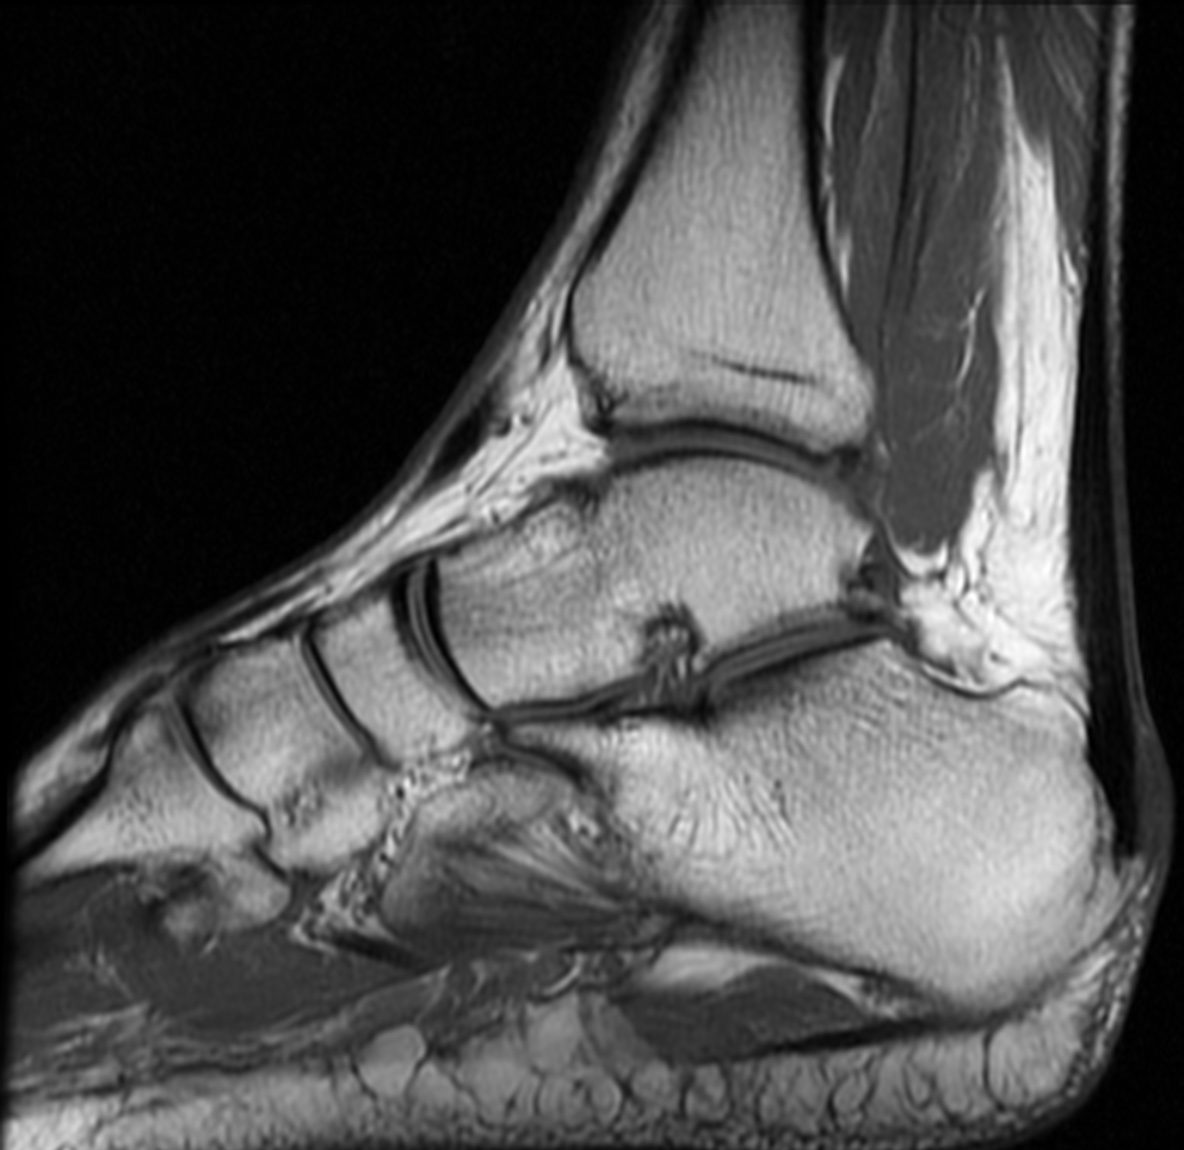

Resonancia Magnética:

- Engrosamiento focal y alteración de señal en la inserción del tendón de aquiles al calcáneo.

- Bursitis retrocalcánea y rotroaquílea.

- Edema de médula ósea en la tuberosidad calcánea.